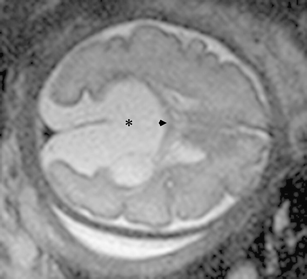

Aicardi syndrome is an X-linked dominant disorder characterized by the pathognonomic association of three clinical signs: agenesis of the corpus callosum, infantile spasms, and chorioretinal lacunae. This is a severe syndrome with an estimated survival rate of 76% at 6 years and 40% at 14 years and a maximum developmental level like a 12-month-old baby in 91% of cases. We illustrate a case of Aicardi syndrome with bilateral, small chorioretinal lacunae, infantile spasms with a typical hypsarrhythmia, defects of thoracic vertebra and bilateral absence of the12th rib associated with an arachnoid cyst of the quadrigeminal cistern, and presence of the corpus callosum with a favorable outcome.

Fig. 2